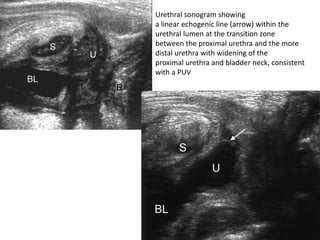

Urethral sonogram showing

a linear echogenic line (arrow) within the

urethral lumen at the transition zone

between the proximal urethra and the more

distal urethra with widening of the

proximal urethra and bladder neck, consistent

with a PUV

• Postnatal ultrasound •Following birth, findings are the same as those on antenatal ultrasound, although as patients who present after birth usually have less severe obstruction, the features may be less evident: • examination of the posterior urethra can be performed longitudinally through the perineum. Ideally this is performed during micturition (which may take some patience) at which time the proximal urethra can be seen to dilate;diameter of more than 6mm is considered abnormal and is highly specific and sensitive to the diagnosis (sensitivity 100%, specificity 89%, positive predictive value 88%) • additionally the valve may actually be seen as an echogenic line

• 58.

Urethral sonogram showing alinear echogenic line (arrow) within the urethral lumen at the transition zone between the proximal urethra and the more distal urethra with widening of the proximal urethra and bladder neck, consistent with a PUV